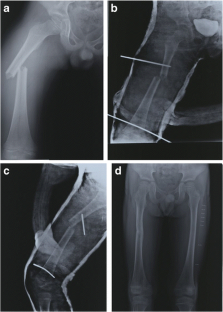

Fig. 1